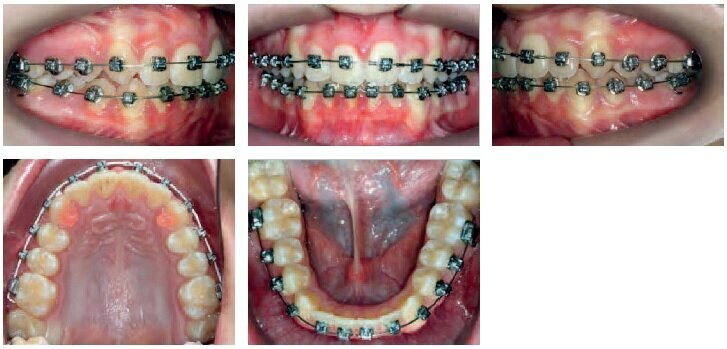

This “spread-out” scheduling approach can also be applied to treatments involving extractions. In this case, the patient moved to Canada in the middle of her treatment (at 11 months), still with several spaces left to be closed. Having already undergone an initial 3 year treatment (see photos), the patient wanted to remain with the same orthodontist and agreed to travel from Canada every 6 months to continue her treatment.

After moving away, she was seen just 3 more times, including the debonding appointment.

At 11 months of treatment, when the patient moved to Montreal

6 months later (at 17 months)

6 months later (at 23 months)

Photos taken at the end of treatment (total of 23 months – 2 appointments in 12 months)